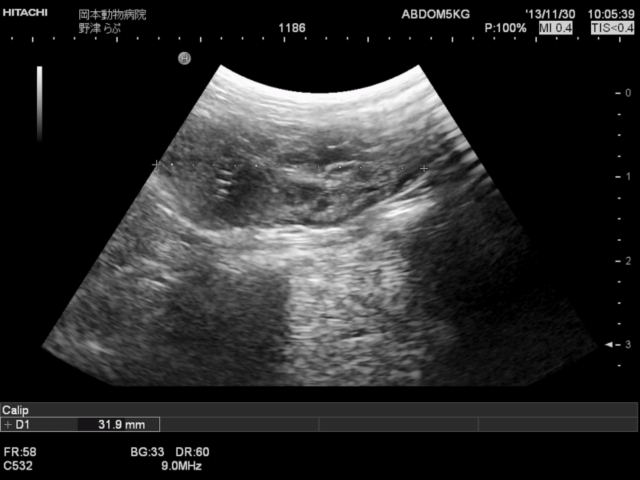

その結果、あちらこちらに異常所見が見つかりましたが、最も重要な所見として卵巣の異常を指摘しました。

そして手術となったわけですが、腹腔内には血様腹水があり卵巣はもちろん、膀胱・腹膜まで播種(細かな転移巣)が見られました。

卵巣は病理検査の結果卵巣がんということでしたので、予後不良と判断したのですが、こちらの意に反して犬は術後すこぶる元気となり食欲も旺盛となりました。